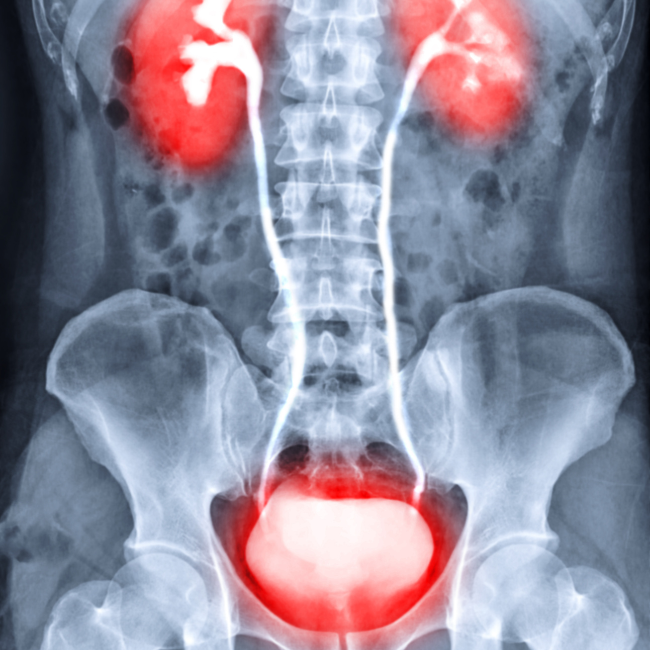

과민성 방광(overactive bladder, OAB)이란 요로 감염 등 다른 명확한 원인이 없는 상태에서 요절박(절박뇨, 강하고 갑작스럽게 소변을 보고 싶은 느낌)이 나타나며 주간 빈뇨와 야간뇨를 흔하게 동반하는 질환을 의미합니다. 생활의 질을 떨어뜨리는 과민성 방광 증후군의 원인과 증상 치료 그리고 자가진단법까지 알아보겠습니다.

과민성 방광 증후군의 원인

과민성 방광 증후군(Interstitial Cystitis, IC)은 정확히 알려진 원인이 없는 만성 방광 질환으로, 다양한 요인이 기여할 수 있습니다. 몇 가지 가능성 있는 원인은 다음과 같습니다: